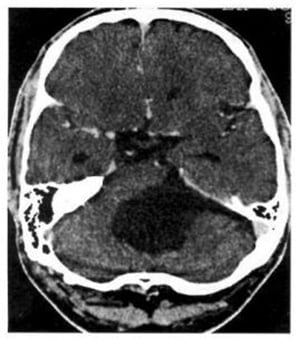

Hình 1.68. Xuất huyết trong não thất. Não thất 4 chứa máu, giãn nở và có mật độ cao (mũi tên). Các sừng thái dương giãn nở chứng tỏ có tắc nghẽn.